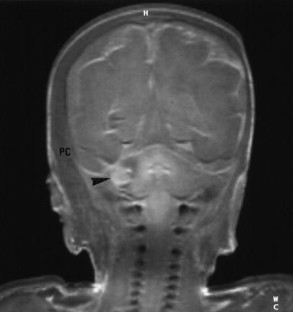

The purpose of this paper is to describe brain pathology in neonates after major traffic trauma in utero during the third trimester. Our patient cohort consisted of four neonates born by emergency cesarean section after car accident in the third trimester of pregnancy. The median gestational age (n=4) was 36 weeks (range: 30–38). Immediate post-natal and follow-up brain imaging consisted of cranial ultrasound (n=4), computed tomography (CT) (n=1) and post-mortem magnetic resonance imaging (MRI) (n=1). Pathology findings were correlated with the imaging findings (n=3). Cranial ultrasound demonstrated a huge subarachnoidal hemorrhage (n=1), subdural hematoma (n=1), brain edema with inversion of the diastolic flow (n=1) and severe ischemic changes (n=1). In one case, CT demonstrated the presence and extension of the subarachnoidal hemorrhage, a parietal fracture and a limited intraventricular hemorrhage. Cerebellar hemorrhage and a small cerebral frontal contusion were seen on post-mortem MRI in a child with a major subarachnoidal hemorrhage on ultrasound. None of these four children survived (three children died within 2 days and one child died after 1 month). Blunt abdominal trauma during pregnancy can cause fetal cranial injury. In our cases, skull fracture, intracranial hemorrhage and hypoxic-ischemic encephalopathy were encountered.